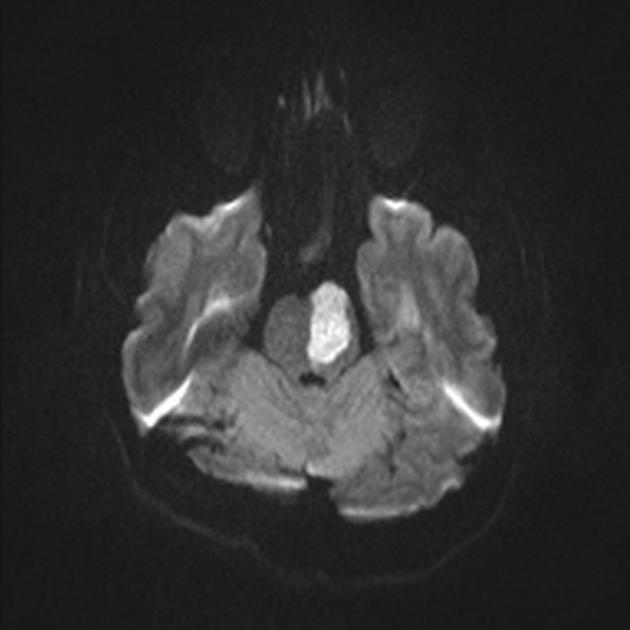

image

In this MRI image of the brain there is a region which has sufferd from and acute infarction/stroke. Can you recognize the region? if you can can , which are the structures (nuclei, pathways) that are most likely affected by the lesion and what could be the possible neurological outcomes in this patient ?

View this question